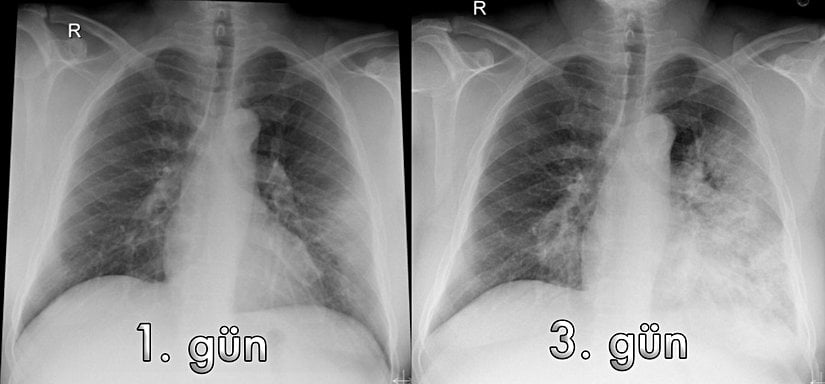

Diğer enfeksiyon ajanları gibi kan veya alt solunum yolu salgılarında (bronkoalveoler lavaj) virüsün ve özgül antikorların tespiti ile tanı konur. Bu yöntemler arasında başlıca rRT-PCR ve ELISA kullanılır. Aynı zamanda laboratuvar testleri arasında enfeksiyon belirteçleri ve akut faz reaktanları da şüphe etmekte yardımcıdır. Ancak ilginçtir ki viral enfeksiyonlarda (ve bazı kanserlerde) yükselen lenfosit sayısının MERS-CoV enfeksiyonunda düştüğü rapor edilmiştir. Ayrıca BT (Bilgisayarlı Tomografi) gibi görüntüleme yöntemleri ile akciğerdeki infiltrasyonlar gösterilerek tanı lehine yorum yapılabilir. En önemli araçlardan biri anamnez adı verilen hasta hikayesidir. Hastanın Orta Doğu'ya seyahati sırasında deve ile teması sorgulanır ve son zamanlardaki diğer seyahatleri araştırılır.